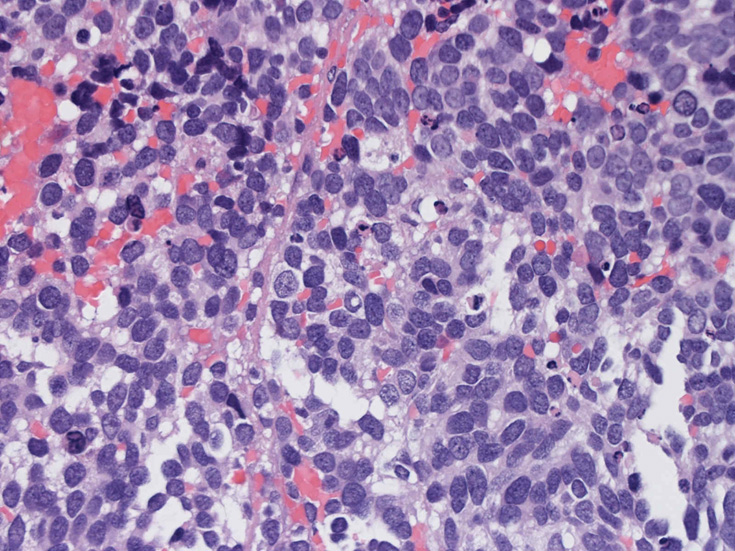

30歳代男性 鼻腔腫瘤の生検組織

厳密にはalveolar patternが明らかではなく, solid typeに入る症例かもしれない。異型細胞増殖胞巣が線維化組織に取り囲まれるように散在している. 小さな生検組織のため全体像が不明である。